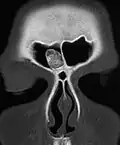

Osteoma of the frontal sinus on CT -